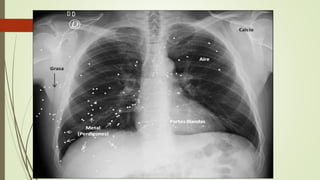

DENSIDADES RADIOLOGICAS

Aire: negro.

Grasa: Gris

más oscuro.

Agua / Partes

Blandas: Gris

claro o palido

Calcio /

Hueso:

Blanco.

Metal: blanco

opaco

RADIOLOGIA 2.0 HERRAMIENTAS PARA EL ANALISIS DE LAS IMAGENES MEDICAS /densidades radiológicas/Dr Mostafa Mahmoud El-Feky

and Dr Jeremy Jones et al. Radiology for students (curriculum) disponible en línea en Radiopaedia.org